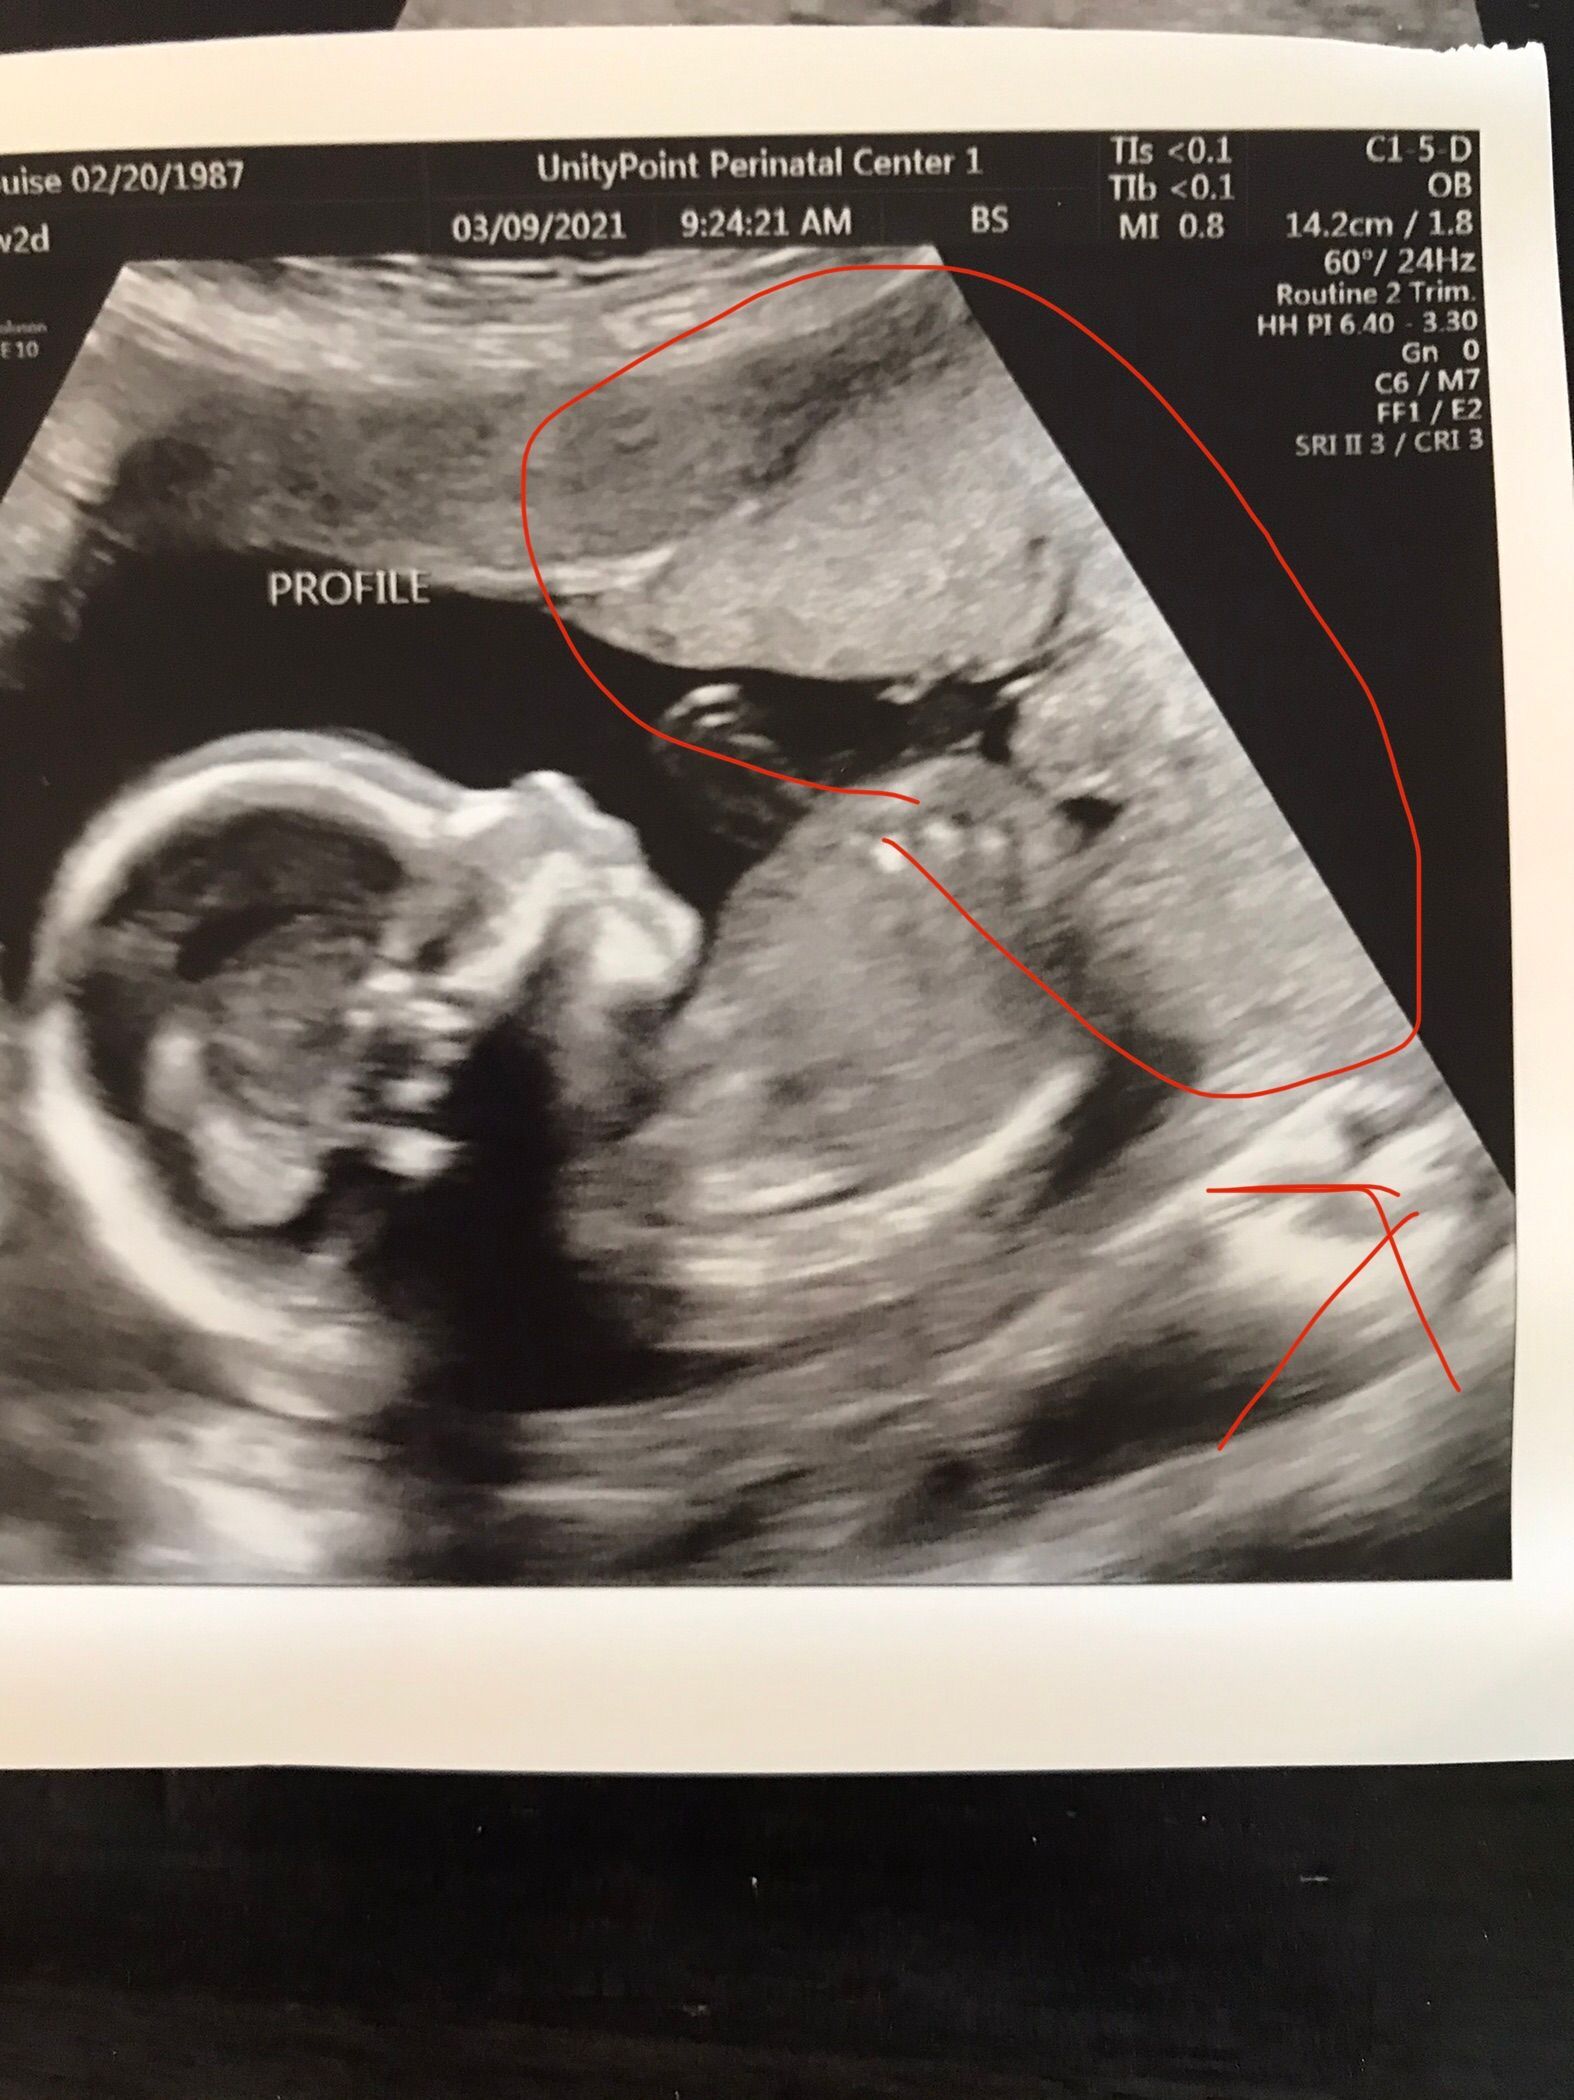

We had our first official doctors appointment! Everything looks good and my due date is July 25th, 2021. It has been a rough first trimester but I am slowly starting to feel better. It was so fun to see our baby and I was amazed at how far along baby seems. Baby is not just a blob but actually looks like a baby!

We had our 20 week ultrasound and found out we are having a girl!!! We are excited but nervous. We don't know how to raise a girl. My placenta is partially over my cervix so we have to have another scan in a few weeks to make sure it moves far enough away so I can have a vaginal birth. They don't seem concerned and think it will move with no problems.